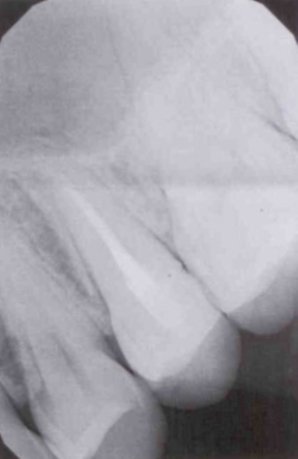

Когда снова пришла, он запломбировал каналы и поставил пломбу. И уже третий день подряд болит зуб. То сильная боль, то терпимая. Перепадами. Когда уже не могу терпеть, пью обезболивающие. Еще принимаю противовоспалительные.

Скажите, должны быть такие боли и пройдут ли они, или это признак воспаления и нужно перепломбировать все?

Конечно, при постоянной пломбировке зуб беспокоить уже не должен. Судя по методам лечения, у вас обострение хронического периодонтита, но оставлять открытым канал на полоскание нельзя, это неграмотное лечение. А также беспокойство зуба, возможно, связано с недолеченным процессом хронического воспаления, обратитесь к другому стоматологу на лечение данного зуба.